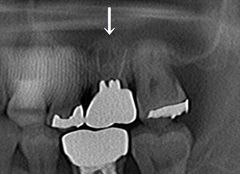

2018/11/20

メタルフリー治療

左上第一大臼歯の銀歯とメタルコアを除去した内部です。2018.11.20